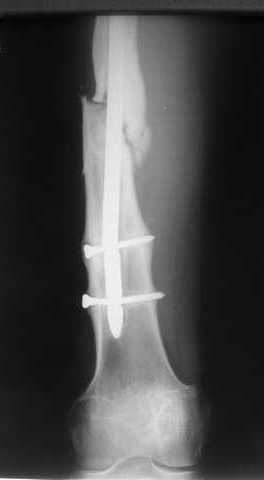

Спицы оставлять не надо. Надо их убрать, но перед этим ввести винт-poller. Такая необходимость возникает в редких случаях, когда можно ожидать смещения длинного отломка. Спицы из короткого отломка после введения запирающих винтов можно удалять без риска смещения.

В приложении пример, дистальный отломок пружинил кзади. Два винта потому, что первый оказался чуть кпереди и не упирался в гвоздь.